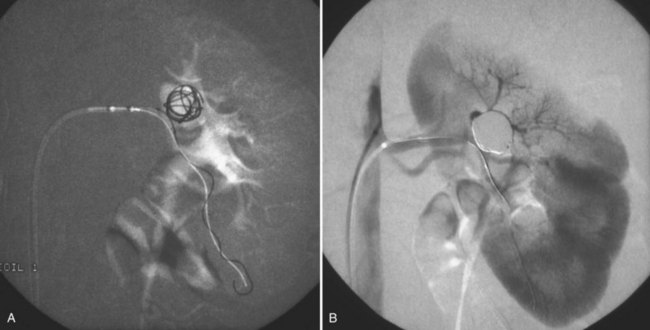

Since its introduction in the early 1970s, renal artery embolization (RAE) has been employed for palliation of inoperable renal tumors, to control bleeding, and as part of multimodal treatment of hypervascular metastatic disease (Almgard et al, 1973). In addition, RAE is used as a preoperative adjunct to resection of locally advanced renal tumors, with or without metastases (Paster et al, 1975) (Fig. 54–15).

Figure 54–15 A, Aortogram in a patient with a left hypervascular renal mass. Note the pooling of contrast medium in the upper pole. B, Left selective artery angiogram before coil placement. C, Aortogram after coil placement demonstrating abrupt cutoff of flow from the left renal artery.

Proposed benefits of preoperative RAE include shrinkage of an arterialized tumor thrombus to ease surgical removal, reduced blood loss, facilitation of dissection due to tissue plane edema, ability to ligate the renal vein before the renal artery at time of nephrectomy, and modulation of the immune response (Klimberg et al, 1985; Bakal et al, 1993; Kalman and Varenhorst, 1999; Schwartz et al, 2007; Wotkowicz and Libertino, 2007; Wszolek et al, 2008). Ligation of the renal vein before the renal artery is useful in the setting of hilar tumors, tumors with significant medial extension, or considerable perihilar adenopathy (Schwartz et al, 2007; Wotkowicz and Libertino, 2007; Wszolek et al, 2008). Before ligating the renal vein, one should characterize the completeness of embolization to prevent unnecessary blood loss in cases of incomplete embolization. In the senior author’s experience this assessment can be made by evaluating renal venous return during surgery. In addition, angioembolization can also be useful for renal tumors associated with large arteriovenous malformations that are having a deleterious hemodynamic impact (Figs. 54-16 and 54-17).